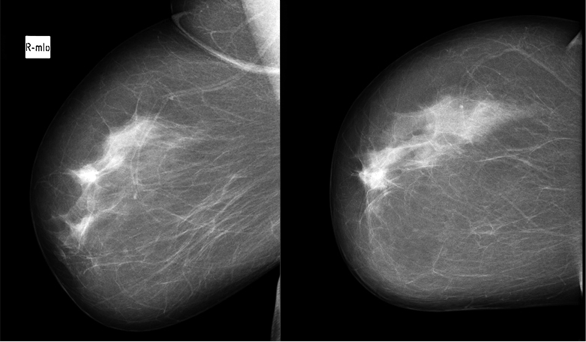

During physical examination a 2 cm hard, not tender, with ill-defined margins lump in the upper inner quadrant of the right breast has been found. There was no nipple retraction, discharge or skin change. A breast ultrasound showed a 1.24x0.85 cm suspicious ill-defined hypoechogenic lesion at 1 o’clock position of the right breast (Figure 1). Mammogram revealed a local hyperdense zone in the right breast (Figure 2). Histopathological examination of the tumour core biopsy material revealed desmoid type fibromatosis. The patient underwent wide local with clear margins excision of the lesion. Histopathological examination of surgical material confirmed desmoid type fibromatosis (Figure 3). Tumour was poorly demarcated, composed of spindle-shape myofibroblasts arranged in long sweeping fascicles. There was no mitotic activity. Immunohistochemical findings of the mass showed a focally positive reaction with beta-catenin, and a negative reaction for CD34, Desmin, CK. The patient did not require any adjuvant treatment. There was no recurrence after two years of follow-up.

Fig. 2. Local hyperdense zone was seen in mammogram

Mammographically breast desmoid tumour appears as a speculated mass [4, 8]. Moreover, rarely it may demonstrate calcified deposits [4]. Magnetic resonance imaging (MRI) is the best radiological diagnose method for diagnosing desmoid tumour [5]. On MRI images desmoid tumour may look as ill-defined hypointense or isointese masses on T1-weighted images or hyperintense masses on T2-weighted images [2].